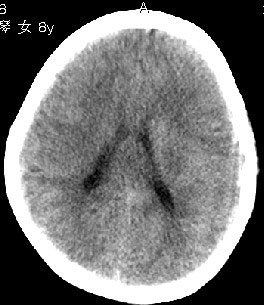

杨某,女,8y,家长述2006.10.13行破伤风疫苗注射后下肢疼痛,后自行粘贴膏药未见好转

,后续发现左上肢肢力下降。于2006.10.28在我院行ct检查,发现右侧基底节区片状低密度影,

无占位效应。ct值约:18~20hu。边界清晰,与相邻脑室无通连。未行增强扫描。余脑实质

未见异常。

右侧内囊后支、丘脑见片状低密度区,边界不清,无占位效应。

从ct图像看,准确地说病变是在右侧丘脑,累积右侧内囊后肢。